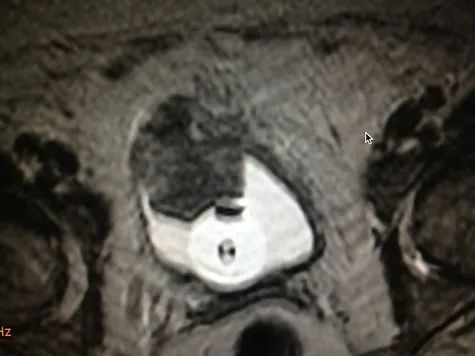

A hormone-secreting tumour that can occur in the adrenal glands. Phaeochromocytomas usually develop in the small glands on top of the kidneys (adrenal glands). They most commonly affect people between the ages of 20 and 50, but can occur at any age. Because of hormones secreted, symptoms include high blood pressure, sweating, rapid heartbeat and headache. Surgery to remove the tumour is usually required.